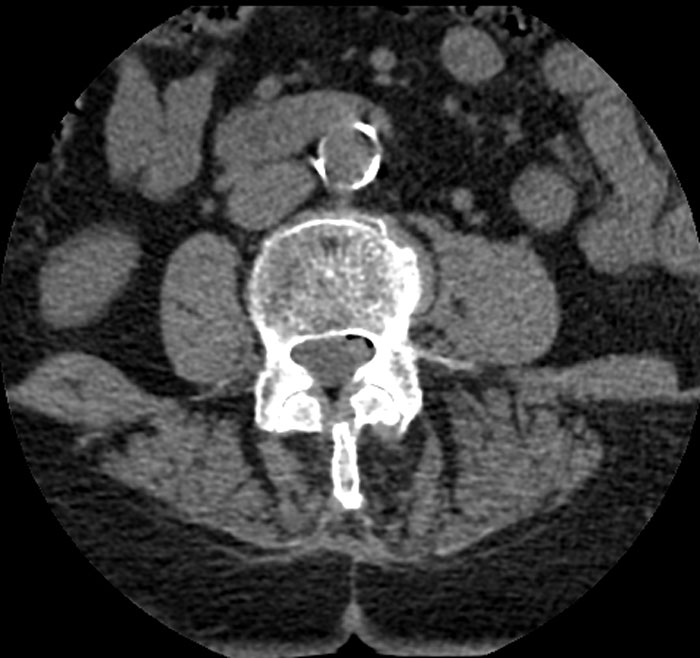

A horseshoe kidney, both kidneys were fused at the lower ends. Another person had a missing lung lobe, so two lobes on each side, instead of two and three (without having had any surgery).

Horseshoe kidneys ☺️ have seen this twice in my 10 year mortuary career. Huge pericarditis pus build up that was 500ml in volume and bright green. Intestines that had herniated into a man’s testicles. Have seen many accessory spleens which are very cute 🥰 I have so many other cool things but these rank up there. Oh just wanted to add that jumping maggots are a thing, fun times!

I don’t perform autopsies but I know someone with three kidneys that they have had since birth. Extremely rare.

Edit: I googled it before I posted and google AI says that like 100 people on earth have an extra kidney, but according to this post everyone an their mom has 3/4/5/50 kidneys. I dont know what to believe anymore. Would AI lie to me?!

I didn’t perform an autopsy, I’m a med student here, we came across a cadaver where the kidneys were located way too higher than the normal ones, and the spleen was highly distorted in shape.